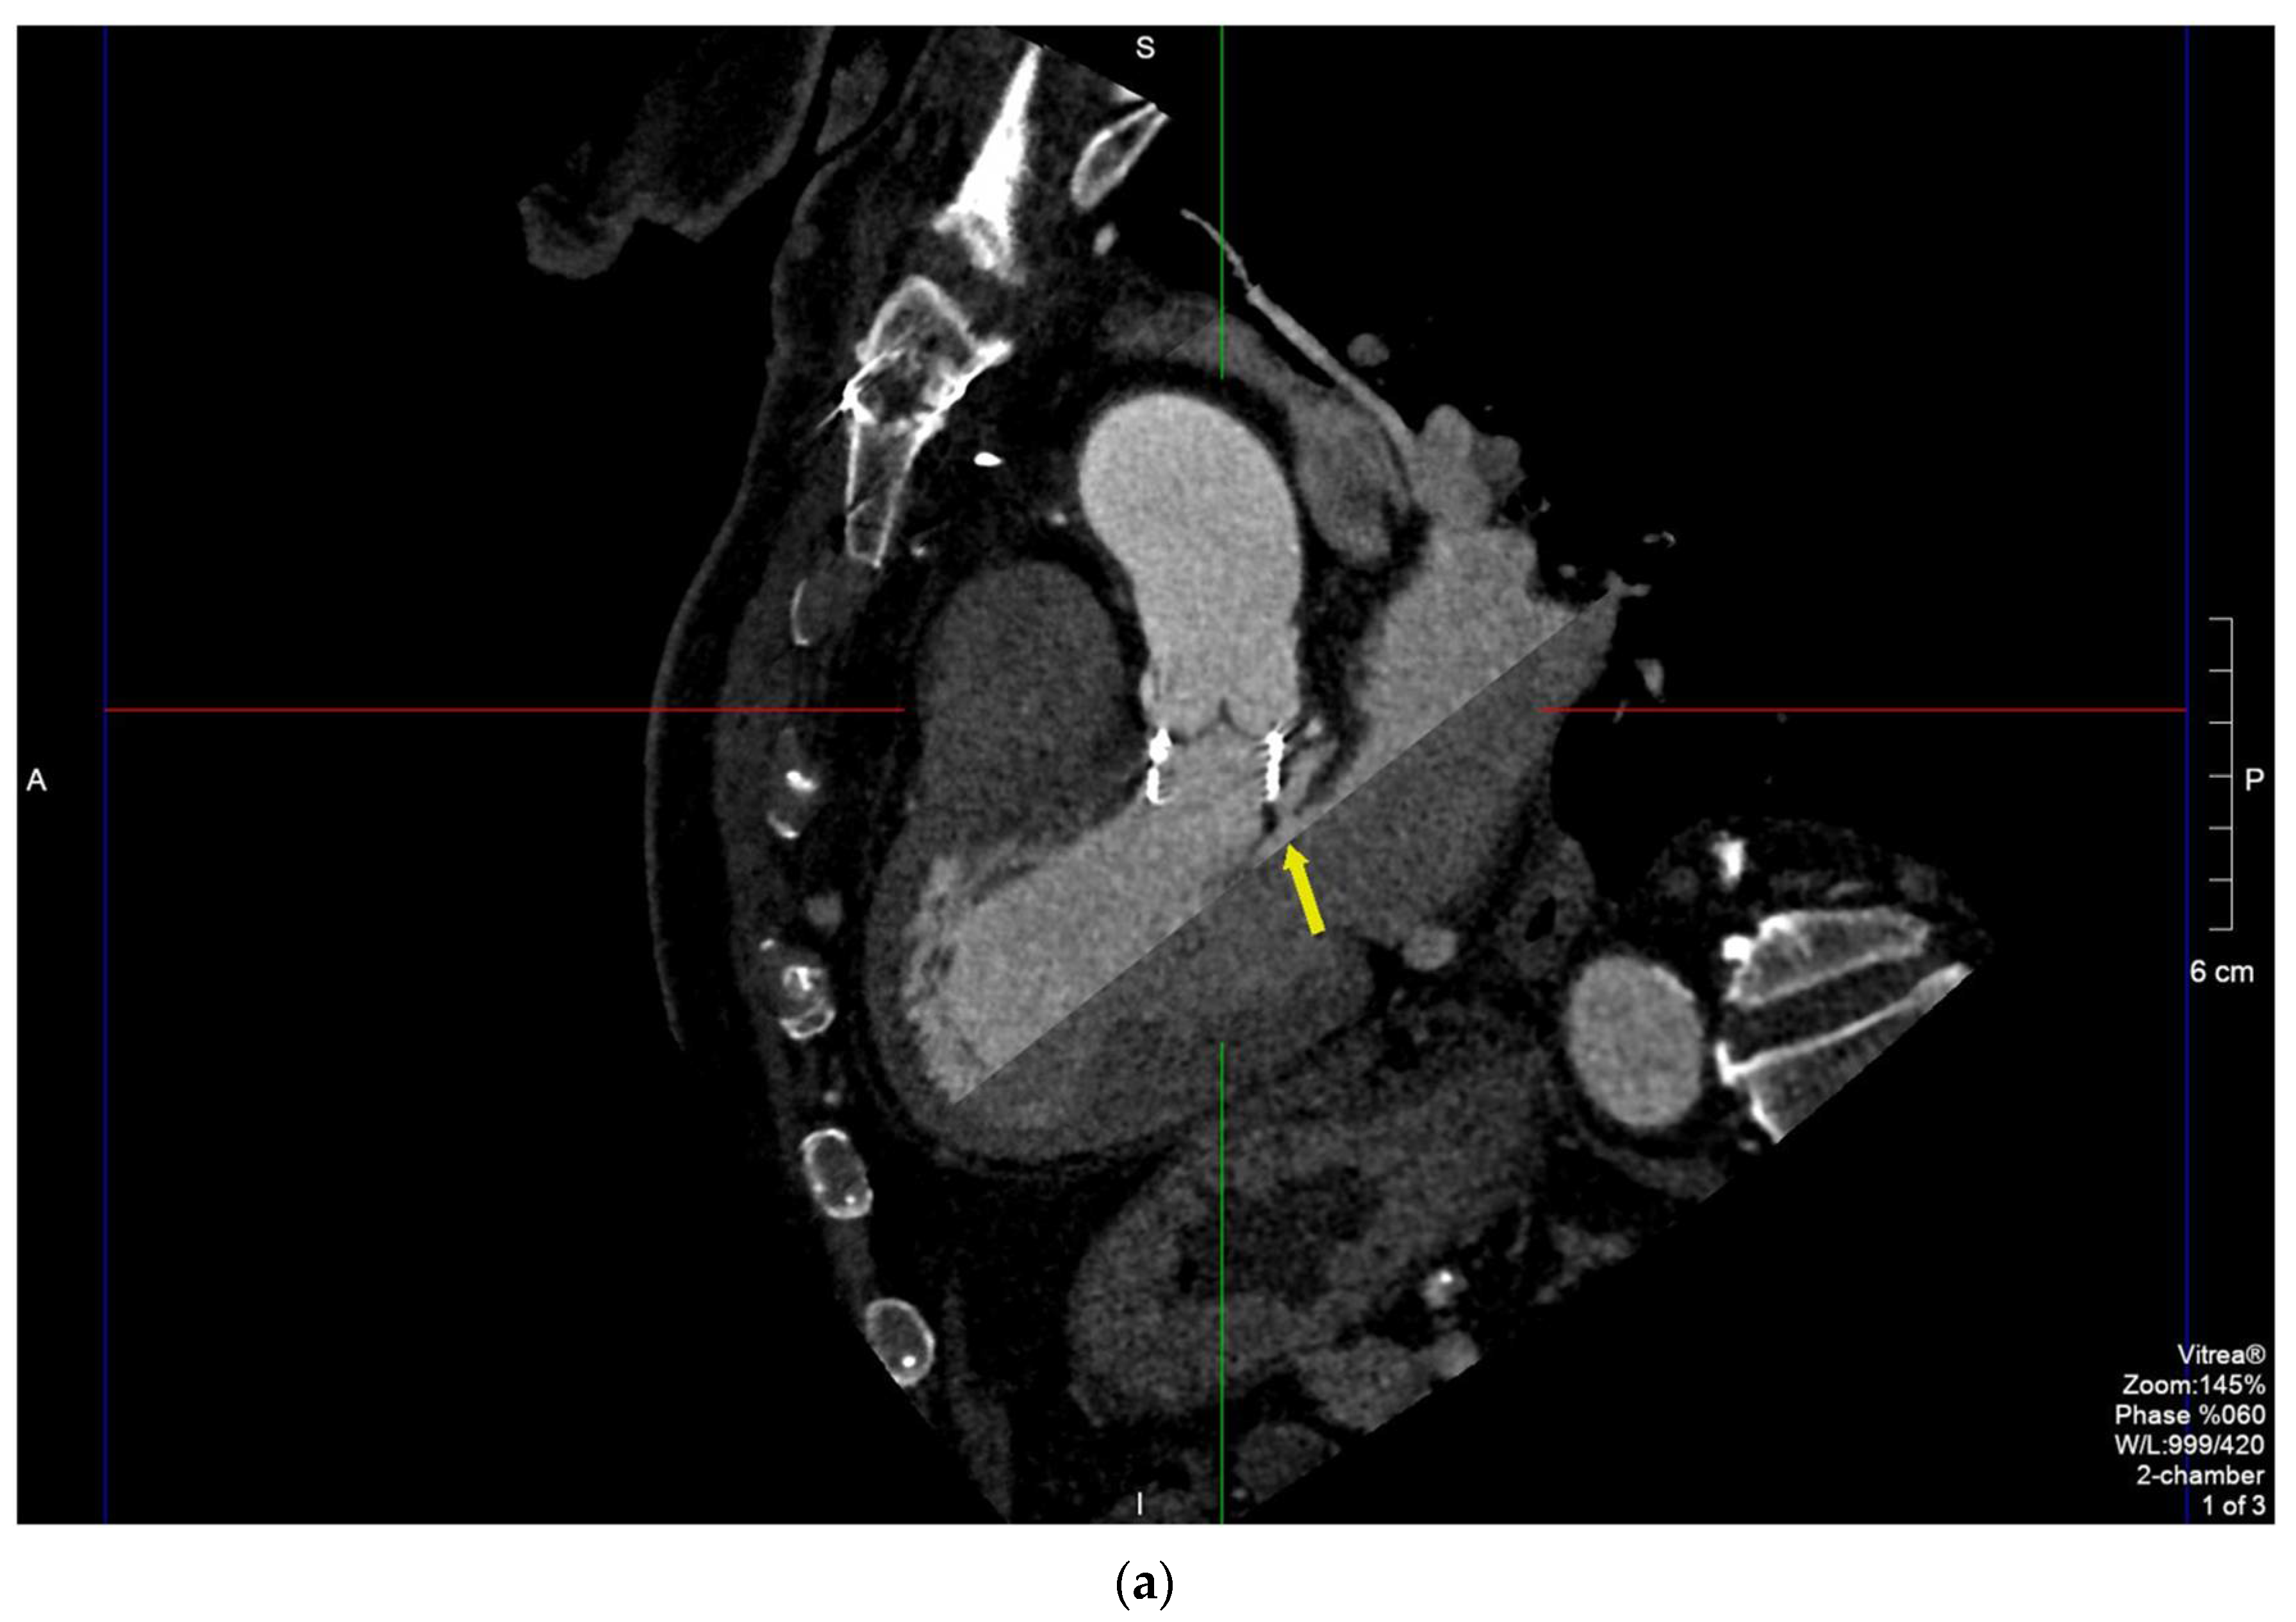

2.2. Case 2

2.3. Case 3

2.4. Case 4